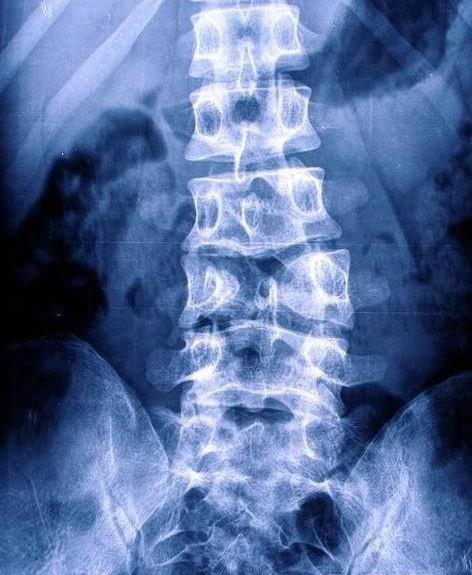

蝴蝶椎

图片尺寸472x575